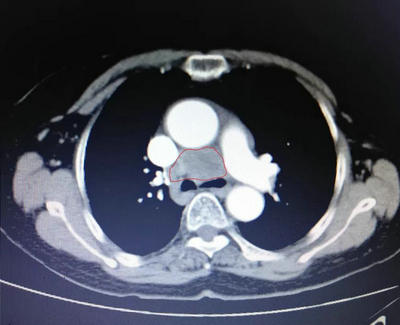

▲ 纵膈占位伽玛刀治疗前和伽玛刀治疗后对比,肿块明显缩小,压迫症状好转